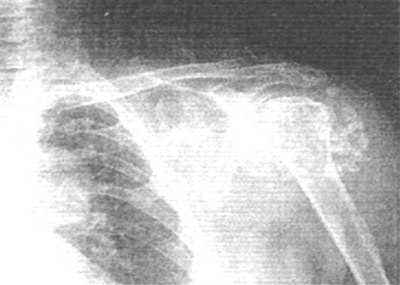

x光表现:所有患者患关节内、旁及周围均可见不同数目的软骨瘤钙化或骨化阴影,其形状、大小和直径从几毫米到几厘米不等。钙化软骨瘤结节的密度和厚度不均匀。较大的钙化或骨化结节的特征是中心密度低,外围密度高,呈石榴状。本组16例患者伴有关节间隙狭窄、关节软组织肿胀和边缘骨质增生(图1)。

图1